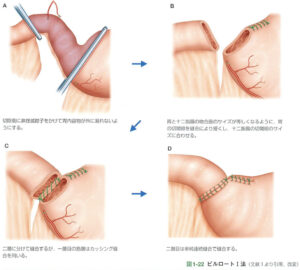

2024.07.23胃がんの診断と外科手術🐕ビルロートⅠ法

ペットの胃の腫瘍について🐾 愛するペットの健康は飼い主にとって非常に大切ですね🐕🐈。最近、ペットの中で胃の腫瘍が話題になっています。実は、犬や猫の胃に腫瘍が発生することは非常にまれで、…